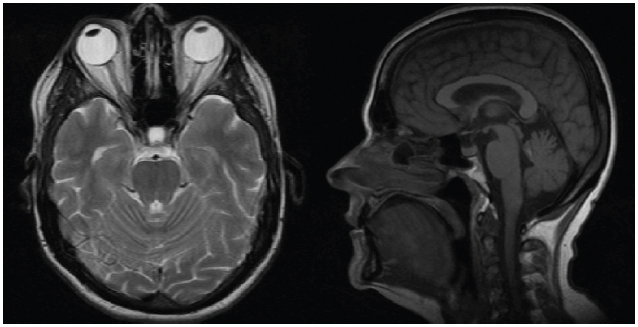

La paciente asistió a controles periódicos hasta 10 meses después del tratamiento. Durante este tiempo refirió mejoría de la cefalea y no se evidenciaron ni deterioro neurológico ni episodios convulsivos; aparte de que mejoró la fuerza de su miembro superior derecho. La RNM cerebral de control reportó una alteración incipiente en el parénquima cerebral, por encima del cuarto ventrículo adyacente y por debajo del vermis, sin que se documentaran realces anormales con la administración del medio de contraste; lo que se correlaciona con el antecedente de radiocirugía (figura 4). Posterior a la realización de la radiocirugía, se inició manejo con trastuzumab entamsine.